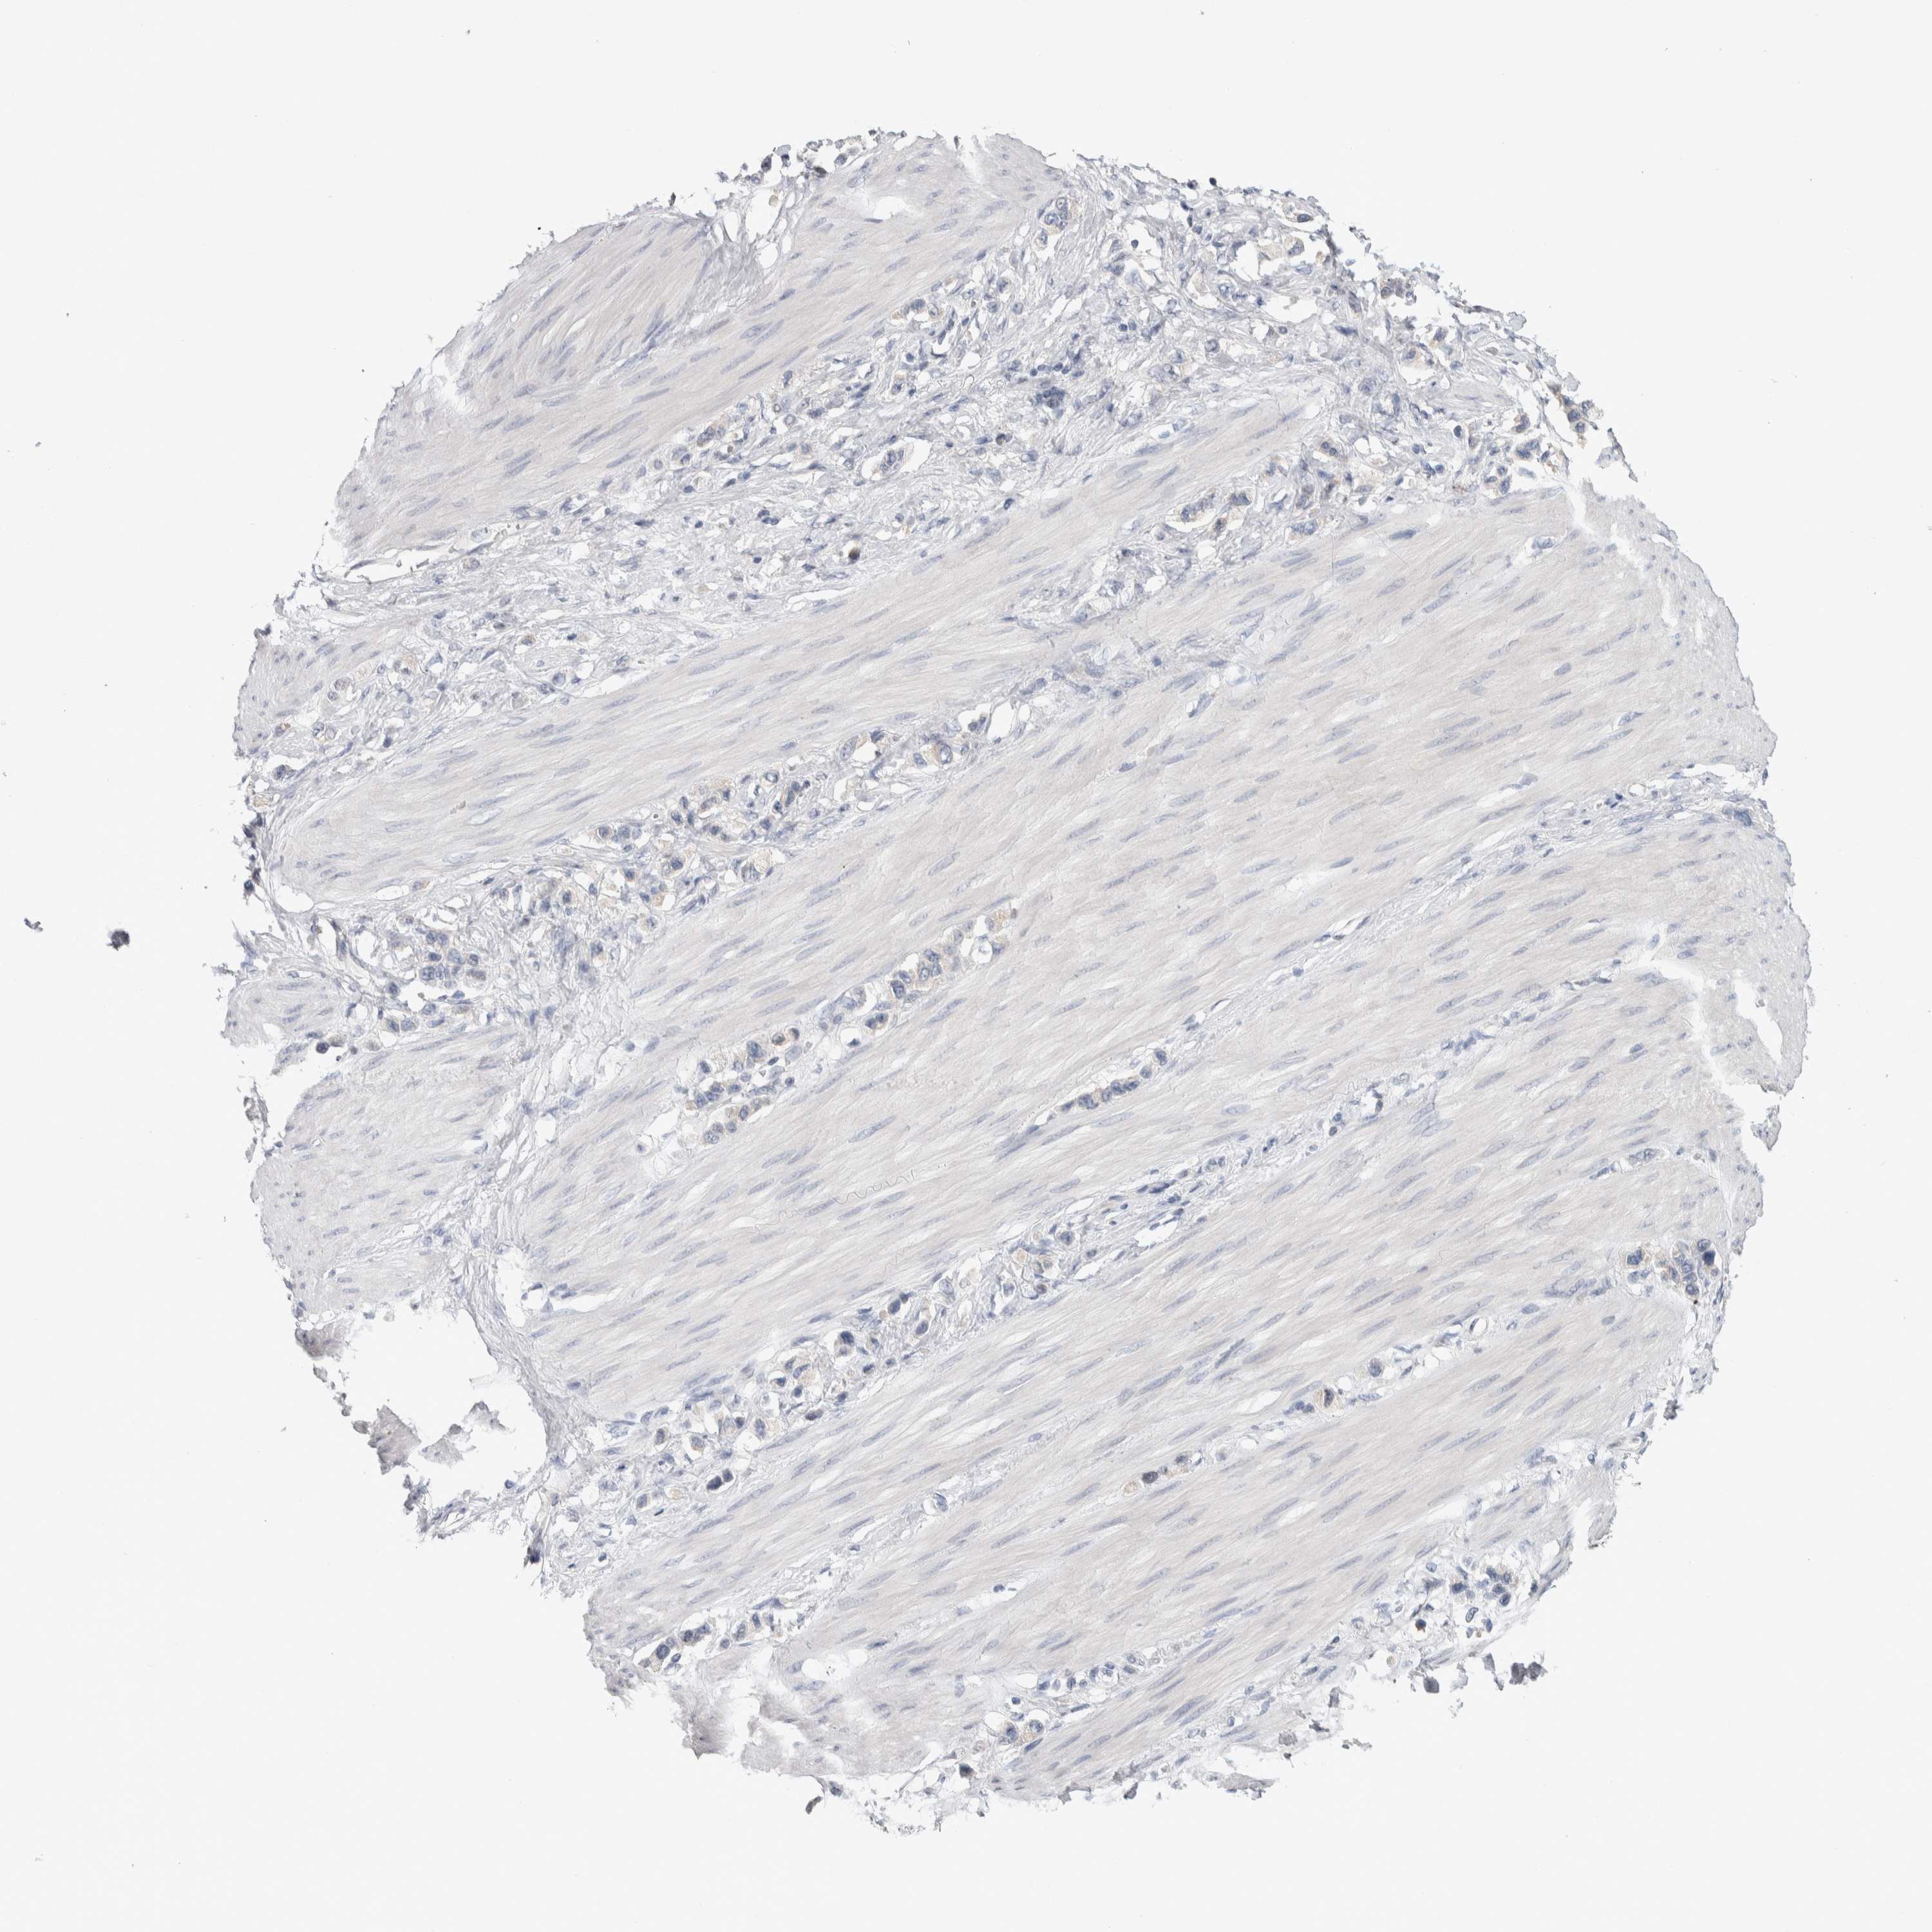

STOMACH CANCER - Protein expressioni

A mouse-over function shows sample information and annotation data. Click on an image to view it in a full screen mode. Samples can be filtered based on level of antibody staining by selecting one or several of the following categories: high, medium, low and not detected. The assay and annotation is described here.

Note that samples used for immunohistochemistry by the Human Protein Atlas do not correspond to samples in the TCGA dataset.

Antibody stainingi

Antibody staining in the annotated cell types in the current human tissue is reported as not detected, low, medium, or high, based on conventional immunohistochemistry profiling in selected tissues. This score is based on the combination of the staining intensity and fraction of stained cells.

Each image is clickable and will lead to virtual microscopy that enables deeper exploration of all samples and also displays staining intensity scores, fraction scores and subcellular localization as well as patient and tissue information for each sample.

Antibody HPA024432

Staining

High

Medium

Low

Not detected

Intensity

Strong

Moderate

Weak

Negative

Quantity

>75%

75%-25%

<25%

None

Location

Nuclear

Cytoplasmic/membranous

Cytoplasmic/membranous,nuclear

Adenocarcinoma, NOS